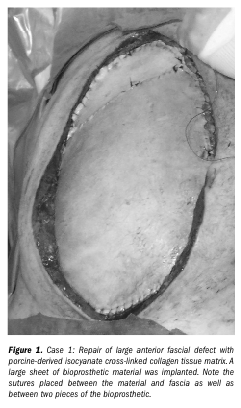

After generalized edema improved and multi-system organ failure resolved, Ms. R was taken for definitive abdominal fascial closure using porcine-derived isocyanate cross-linked collagen tissue matrix (Permacol™, Tissue Science Laboratory, Hampshire, UK). Large sheets of porcine tissue matrix were used to reconstruct the fascial defect that measured approximately 30 cm cephalad to caudad and 20 cm side-to-side. The sheets were approximated using a combination of running and interrupted non-absorbable sutures (see Figure 1). Subcutaneous tissue overlying the porcine tissue material was mobilized and the skin edges were sutured together using 2-0 nylon interrupted mattress sutures. A closed-suction drain was placed underneath the cutaneous flap.